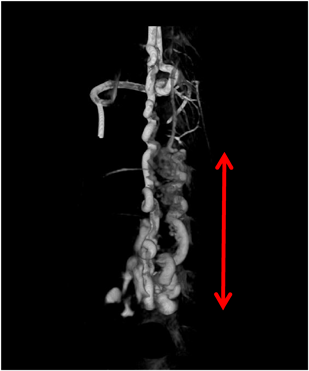

肺動静脈瘻を契機に発見され,脳脊髄動静脈瘻の破裂により死亡した遺伝性出血性末梢血管拡張症の小児2例Hereditary Hemorrhagic Telangiectasia Patients Detected by Pulmonary Arteriovenous Malformations: Two Pediatric Death Cases from Rupture of Cerebral and Spinal Arteriovenous Malformations